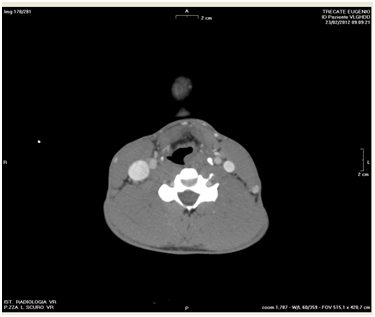

A 39year-old man was struck by a barbell at the cervico-facial junction while exercising at gym. He was referred to our ENT department after a assessment in the Emergency Department. The patient was alert and cooperative and his presenting symptoms were dysphonia, neck pain, odynophagia and dysphagia. He did not complain of shortness of breath, cough or gagging. Examination of the neck did not reveal swelling or surgical emphysema. He underwent flexible nasolaryngoscopy which showed significant swelling of the left side of larynx (left arytenoid, left aryepiglottic fold and left piriform recess). The mobility of the left vocal fold was impaired however there were no signs of compromise of the supra-glottic airway nor injury of the hypo pharynx nor bleeding. A Computerized Tomography with contrast showed isolated fracture of the hyoid bone in the right para-median region (Figure 1) and oedema of the left larynx (Figure 2).

Figure 1 The right para-median region.